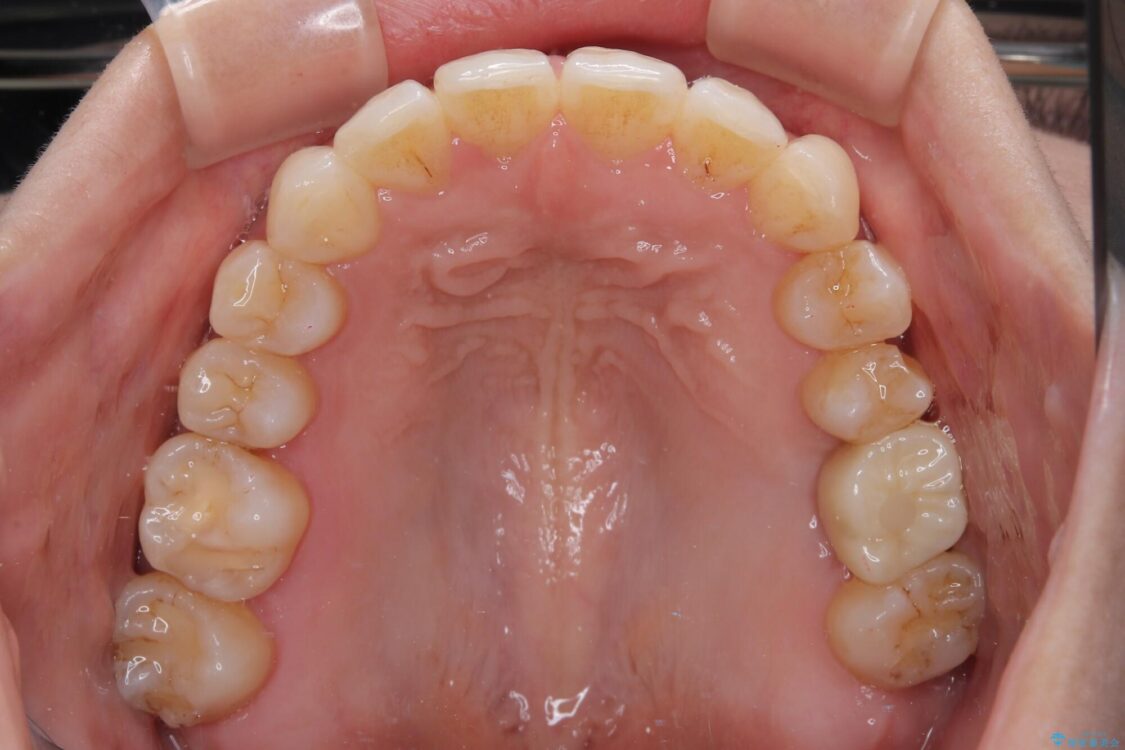

治療途中

• インビザラインによる矯正治療と奥歯のインプラント治療 治療途中画像